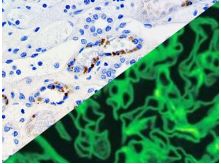

Bio SB has developed a highly sensitive Immunofluorescence and non-biotin monovalent Fab micropolymer IHC detection systems for the detection of IVD antibodies for Complement (C1q, C3c, C3d, C4c, C4d), Serum Proteins (Albumin and Fibrinogen) and Immunoglobulins (IgA, IgD, IgE, IgG, IgM, Kappa and Lambda) related to autoimmune conditions. Our innovative IF and IHC detection systems and high affinity antibodies, have opened the doors for a faster and accurate Immunofluorescence and Immunohistochemistry applicable to Autoimmune Disease like Nephropathies and Lupus.

These antibodies and detection systems are intended for use in Immunohistochemical (IHC) and Immunofluorescence (IF) applications of formalin-fixed paraffin-embedded tissues (FFPE), frozen tissue sections and cell preparations.

Rabbit FluoroDetector FITC |

Rabbit FluoroDetector FITC with FluoroMounter |

Rabbit FluoroDetector FITC with FluoroMounter with DAPI |